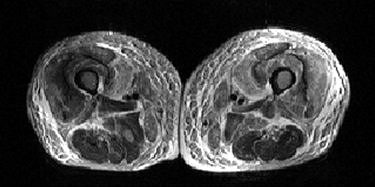

![]() |

| A 59-year-old man with nephrogenic systemic fibrosis (NSF) with both skeletal muscle and skin findings. Axial T1- and fat-suppressed T2-weighted images of thighs show symmetric skin thickening and edema in medial thighs. There is also marked edema in subcutaneous fat, intermuscular fascia, and thigh muscles with some sparing of posterior thigh muscles. Broome DR, Girguis MS, Baron PW, Cottrell AC, Kjellin I, and Kirk GA, "Gadodiamide-Associated Nephrogenic Systemic Fibrosis: Why Radiologists Should Be Concerned" (AJR 2007; 188:586-592). |